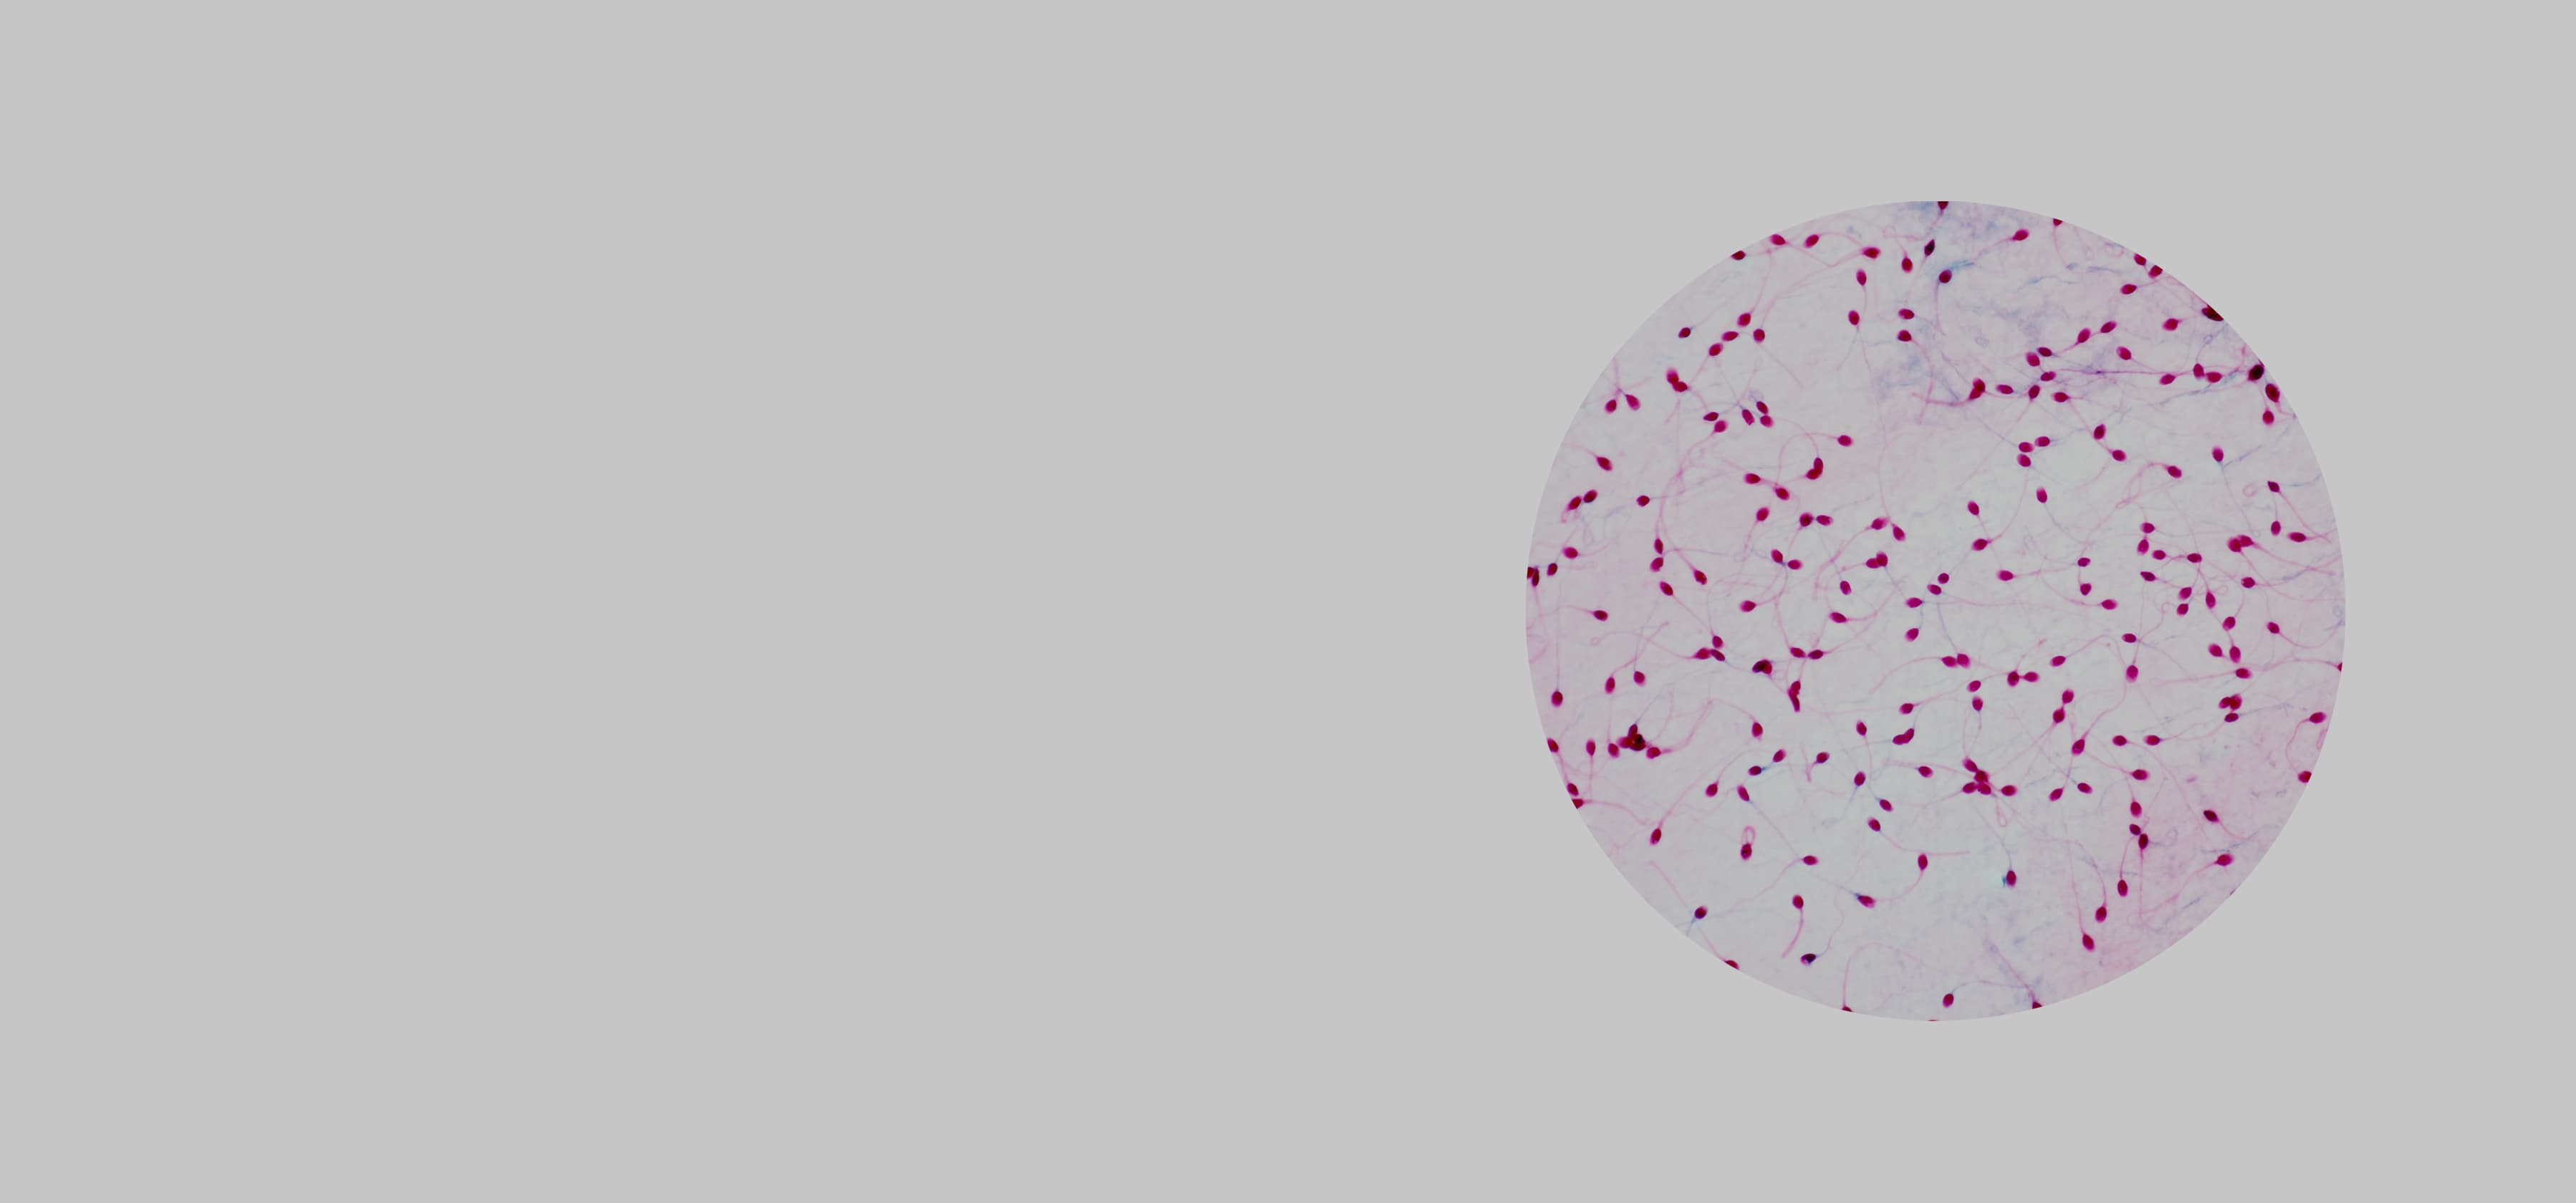

Спермограмма — это анализ спермы. С помощью данного анализа можно оценить функцию половых органов и проходимость семявыносящих путей, а также определиться с дальнейшей тактикой обследования. С ее помощью можно выявить отсутствие сперматозоидов в эякуляте, недостаточную подвижность и концентрацию, заподозрить воспалительные заболевания половых органов и так далее.

Базовый анализ эякулята (спермограмма) учитывает важные параметры эякулята: объем, вязкость, концентрацию сперматозоидов, их подвижность и морфологию.